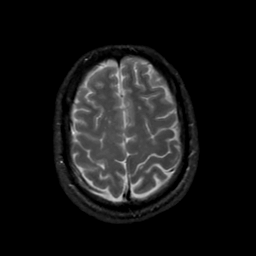

MR Study #20 October 6, 1991 -- Slice #40